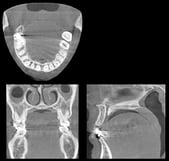

埋まっている親知らずの抜歯やインプラント手術にはCTX線写真